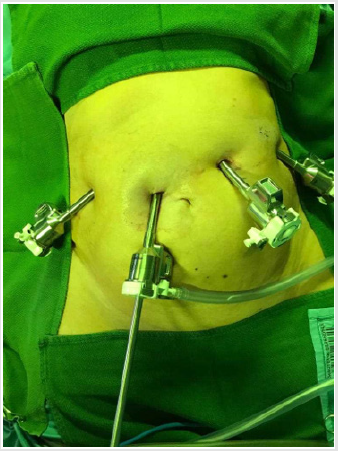

The robotic resection for colon and liver was performed using the “da Vinci robotic X system” (Intuitive Surgical, Inc., CA, USA) in an already described fashion [9-11]. We initiated the procedure with the left hemihepatectomy. Therefore, the robot was initially docked coming from the patient’s right shoulder, while the trocars were placed in the left and right upper abdomen (Figures 4 & 5). During the exploration of the abdomen intraoperative ultrasound was used, in order to determine the extent of liver metastasis, to exclude further lesions in the right liver lobe and to define the resection margins. After successful dissection of the hilar structures, identification of the left sided main vessels (left hepatic artery and left branch of the portal vein), parenchyma dissection was performed using several tissue dissecting devices such as the harmonic. During left hemihepatectomy there was a low blood loss (250 ml) without need for Pringle maneuver. After successful liver resection, we redocked the robotic system in order to proceed with the right hemicolectomy. Docking position and surgical technique including robotic right hemicolectomy, CME and Central Vascular Ligation (CVL) have been described recently [11].

Figure 5: Docking of the da Vinci robotic X system (Intuitive Surgical, Inc., CA, USA) for robotic hemi hepatectomy.